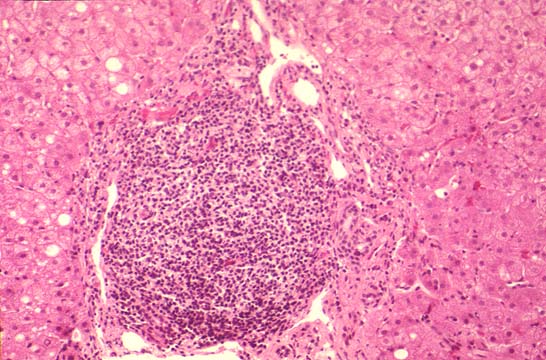

Fig. 115 - Lobular

inflammation.

Viral hepatitis C infection induces the general changes of hepatitis, namely, necroinflammation and fibrosis. These two parameters are morphologically estimated according to the scoring system presented in the discussion of viral hepatitis B. (see contents, li-5-3).As in hepatitis B, the damage of hepatocytes is considered to be immunomediated, (Acadia, Intervirology 37(2):126-132,1994), Although direct viral cytopathogenicity is also probable. A few quantitative differences of pathological changes appear to be associated more with hepatitis C:

1--a mild but constant necroinflammation in the parenchyma.(Gerber, Ver. Deu..Ges. Path. 79:162- 70,1995).( lobular hepatitis).

3--a strong lymphocytic infiltration of portal fields.